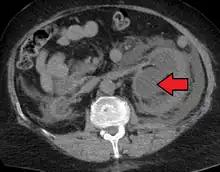

Massive hydronephrosis as marked by the arrow.- Renal ultrasonography of hydronephrosis[14]